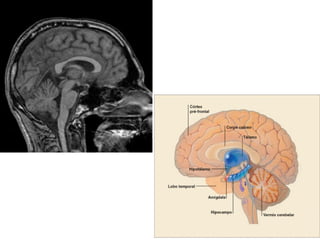

Hipotálamo Control hipoficiarioTRH: libera la tirotrofina. GnRH: Libera las gonadotrofinas. Somastostatina: inhibe la liberación de somatotrofina. Factores que regulan la prolactina.

Liberadas por elhipotálamo y almacenadas en la hipófisis posterior Oxitoxina: Permite las contracciones uterinas. Antidiurética (ADH): disminuye la excreción de agua por los riñones